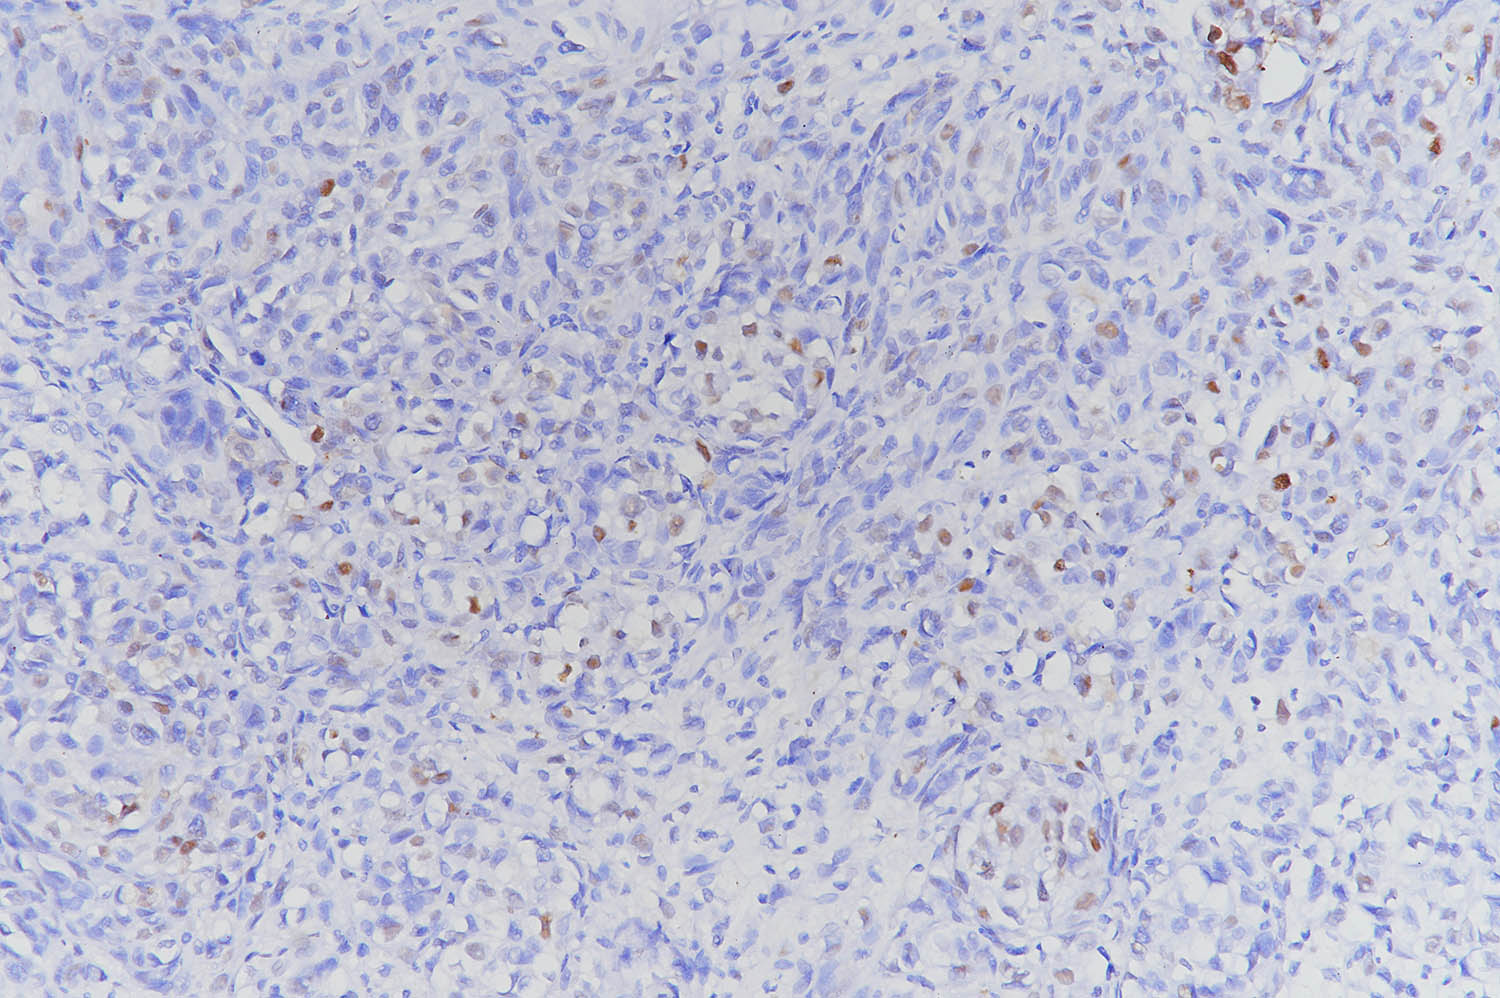

(6)DAB染色3-10min,自来水冲洗,苏木素复染, 1%盐酸酒精分化,显微镜下观察,控制染色程度。

(10)通过显微镜采集分析样本相关部位,计算凋亡率。